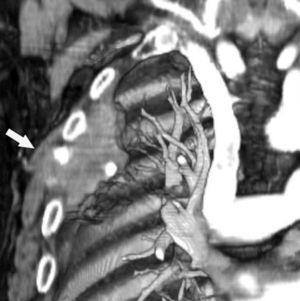

Fig. 3.--Invasión de pared torácica. Tomografía computarizada (TC) torácica con contraste. Reconstrucción coronal con ventana de hueso (A) y de volumen (B). La presencia de destrucción ósea (flecha negra) o de masa en el espacio intercostal (flecha), son los únicos signos fiables de infiltración de la pared torácica.